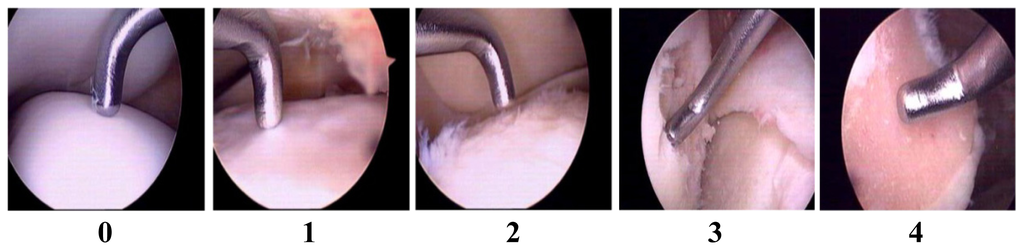

2.1. Validation of Articular Cartilage Lesions in Human Knee Joints Using the Outer-Bridge Scoring System

- Wu, C.W.; Morrell, M.R.; Heinze, E.; Concoff, A.L.; Wollaston, S.J.; Arnold, E.L.; Singh, R.; Charles, C.; Skovrun, M.L.; FitzGerald, J.D.; et al. Validation of American College of Rheumatology classification criteria for knee osteoarthritis using arthroscopically defined cartilage damage scores. Semin. Arthritis Rheum 2005, 35, 197–201. [Google Scholar]

- Cameron, M.L.; Briggs, K.K.; Steadman, J.R. Reproducibility and reliability of the outer-bridge classification for grading chondral lesions of the knee arthroscopically. Am. J. Sports Med 2003, 31, 83–86. [Google Scholar]